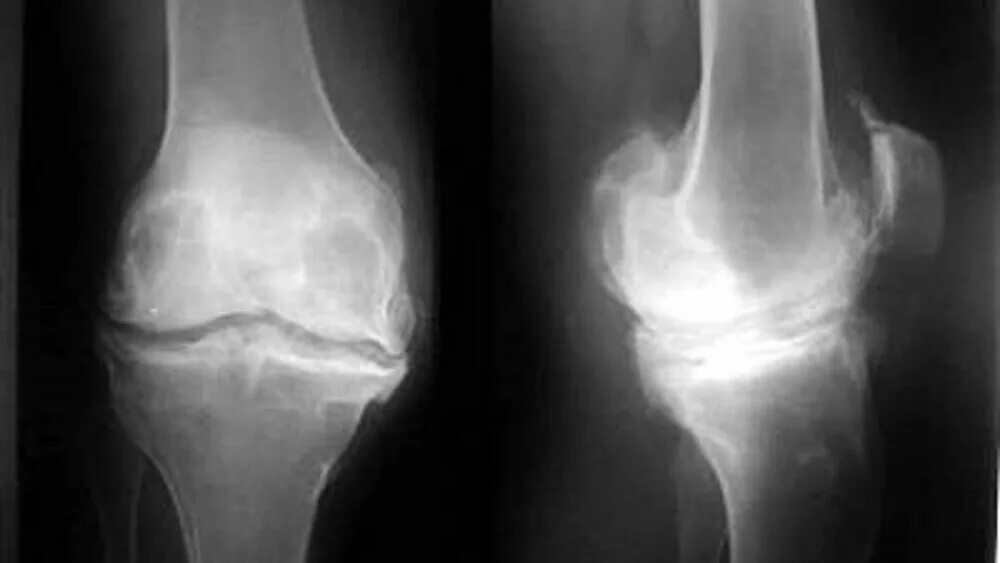

Что такое остеофиты коленного сустава как лечить